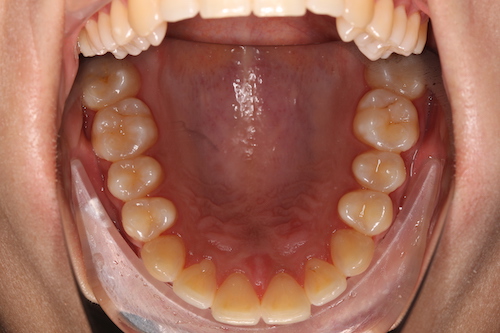

До